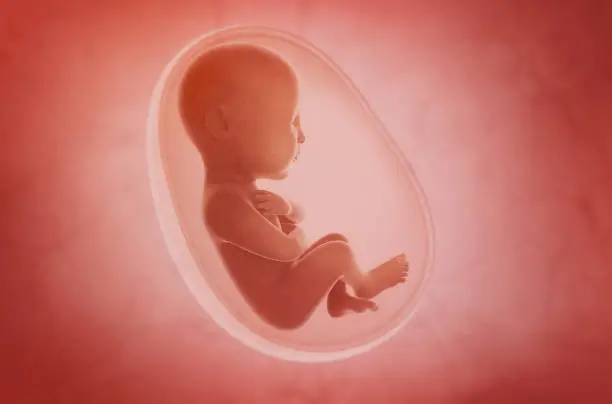

착상혈은 배아가 자궁 내벽에 자리잡을 때 자궁 내막의 작은 혈관이 손상되며 발생하는 출혈입니다. 이는 임신 초기에 나타날 수 있는 자연스러운 현상이며, 일반적으로 수정 후 6일에서 12일 사이에 발생합니다. 착상혈은 보통 소량의 출혈로, 갈색 또는 분홍빛을 띠는 경우가 많습니다. 반면 생리는 수정되지 않은 난자가 배출되면서 자궁 내막이 떨어져 나가면서 발생하는 더 많은 양의 출혈입니다. 생리는 착상혈에 비해 출혈의 양이 많고 지속 시간이 길며, 붉은색을 띠는 경우가 대부분입니다.

착상혈은 짧은 기간 동안 발생하며, 보통 하루나 이틀 정도 지속됩니다. 생리와 달리 착상혈은 통증이나 불편함이 거의 없으며, 생리 주기의 중간이나 후반부에 나타날 수 있어 혼동을 줄 수 있습니다. 그러나 생리는 평균 3일에서 7일까지 지속되며, 생리통과 같은 증상이 동반되는 경우가 많습니다. 또한 생리는 규칙적인 주기에 맞춰 반복되는 반면, 착상혈은 임신이 되어야만 발생하는 일회성 출혈이라는 점에서 차이가 있습니다.